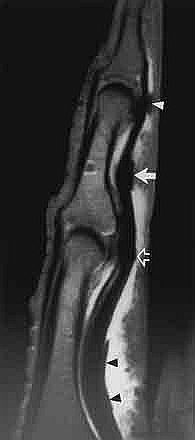

Zda se jedná o úplnou nebo neúplnou rupturu anebo jen natažení (přetažení, distenzi) musí být prokázáno dalšími vyšetřovacími metodami sonografie (přednostně – umožňuje vyšetření při pohybu), ideálně magnetické rezonance. (viz.obrazky)

MRI: ruptura A2